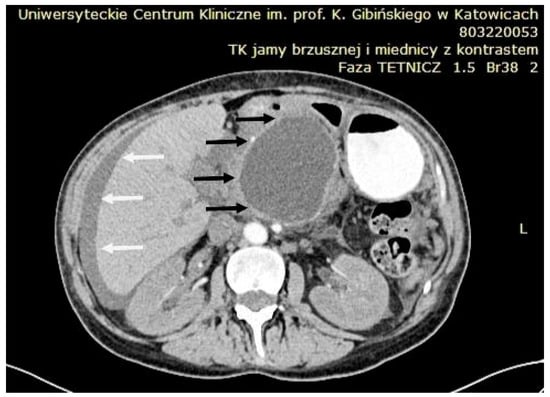

4.1. Percutaneous Drainage (PCD)

6. Endoscopic Drainage of PPCs

6.8. Lumen-Apposing Metal Stents (LAMSs)

6.12. Endoscopic Ultrasound (EUS)

6.14. Transabdominal Ultrasound and CT Imaging